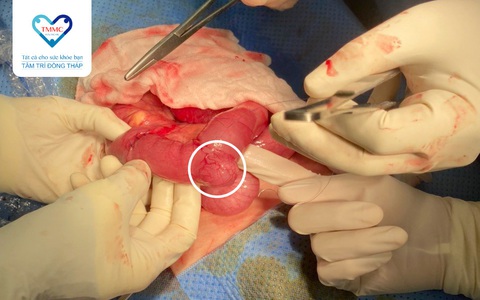

Bệnh viện Đa khoa Tâm Trí Đồng Tháp vừa thực hiện cấp cứu phẫu thuật thành công cho bệnh nhi 7 tuổi bị lồng ruột do polyp hồi tràng gây tắc ruột.